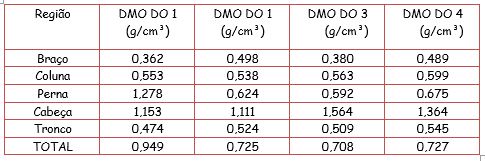

Primeira densidometria óssea (DO1) foi realizada antes do primeiro ciclo com pamidronato dissódico, evidenciando densidade mineral óssea (DMO) de corpo inteiro de 0,949 g/cm², DMO da coluna lombar (vértebras L1-L4) de 0,410 g/cm³ e 26,2% de massa gorda. Após primeiro ciclo do tratamento, segunda DO (DO2) realizada evidenciou DMO de corpo inteiro de 0,725 g/cm², DMO da coluna lombar de 0,460 g/cm² e 13,4% de massa gorda. Após terceiro ciclo com pamidronato dissódico, terceira DO (DO3) mostrou DMO de corpo inteiro de 0,708 g/cm², DMO da coluna lombar 0,547 g/m² e 23,4% de massa gorda. A quarta DO4 (imagem 5) mostrou DMO total de 0,727 g/cm2, DMO(L1-L4) de 0,614 g/cm² e 25,2% de massa gorda.

Após tratamento com ciclos de pamidronato dissódico, que é um potente inibidor da reabsorção óssea mediada por osteoclasto – inibe o acesso de precursores osteoclásticos para o tecido ósseo e sua subseqüente transformação em osteoclastos maduros com atividade de reabsorção óssea, a cada quatro meses, foi possível perceber significativa melhora da densidade mineral óssea (DMO), demonstrada pelo aumento de 35% de massa óssea dos membros superiores (não sendo possível a comparação com MMII visto que o mesmo encontrava-se imobilizado devido a fraturas na realização da DMO antes do ciclo).

O paciente iniciou o tratamento descrito com 2 anos e 6 meses, sendo portanto, um caso relevante devido à escassez, na literatura, de trabalhos acerca do uso de pamidronato dissódico em paciente menores de 3 anos. Também é relevante evidenciar a eficácia terapêutica comprovada após o tratamento, através da evolução dos resultados da DMO apresentadas na tabela 1.